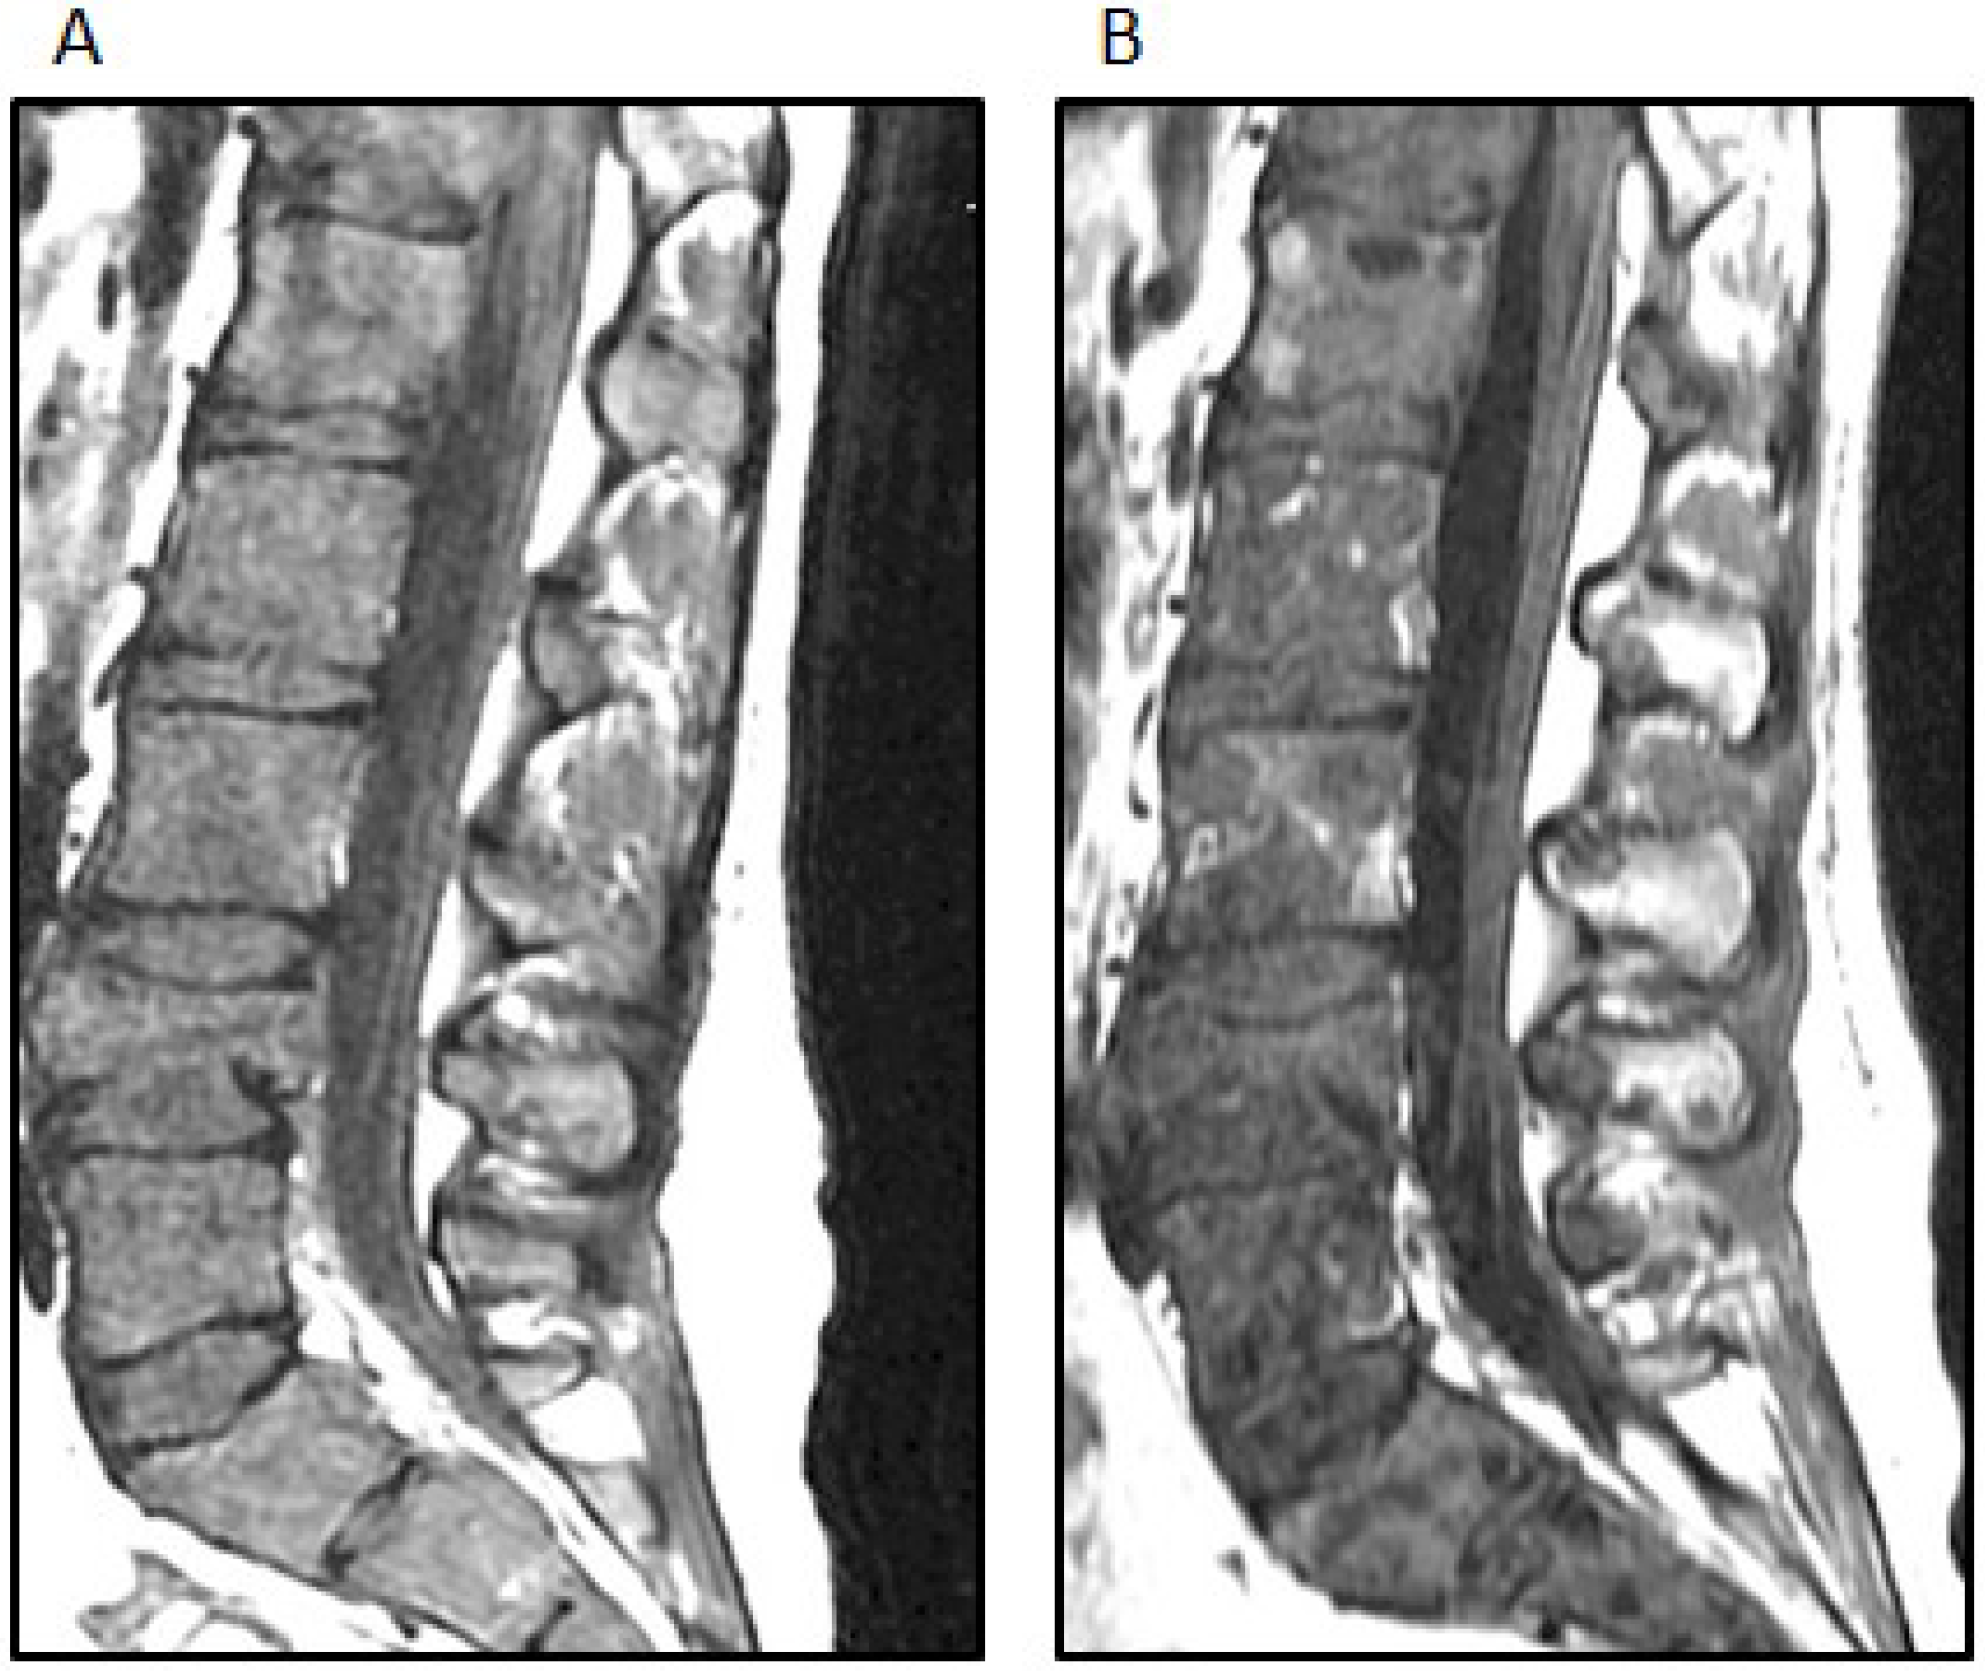

Two weeks after the completion of radiation therapy, the patient developed painless bilateral cervical adenopathy with several firm, immobile, right posterior cervical lymph nodes approximately 2 cm in the greatest diameter. One week later, the patient developed midline back pain primarily in the lumbar area and also pancytopenia. An MRI demonstrated the bilateral cervical adenopathy, as well as lytic vertebral lesions of the cervical, thoracic and lumbar spine with multifocal bone marrow involvement (Figure 4A). A mass deep to the right sternocleidomastoid muscle was excised. Microscopically, there was an infiltrated lymph node along one edge, and the mass consisted of sheets of poorly-differentiated metastatic tumor cells positive for GFAP and rarely for synaptophysin. A right iliac crest bone marrow biopsy was performed, and it showed 60% infiltration with GFAP-positive and nestin-positive tumor cells, while synaptophysin was focally positive (Figure 5).

Figure 4. (A) The sagittal STIR (short TI inversion recovery) MRI image demonstrates extensive new osseous metastases with multiple pathologic compression fractures of the lumbar spine; (B) The sagittal T-weighted MRI image demonstrates interval mild improvement in bone marrow signal abnormality after treatment; the fatty replacement of tumor is shown by white arrows.

This pattern of mutations has been reported in high-grade pediatric gliomas and supported this diagnosis. The presence of a BRAF V600E mutation suggested additional therapeutic options. Following the discussion of this case at the Rutgers Cancer Institute of New Jersey Molecular Tumor Board, vemurafenib (960 mg BID), an oral BRAF inhibitor, was added to her treatment regimen. She developed a macular rash on the extremities five days after starting vemurafenib, while both back pain and pancytopenia improved and the cervical adenopathy regressed. An MRI of the spine also showed partial regression of the bone marrow disease (Figure 4B). After four weeks of this treatment, she developed worsening back and hip pain, and the size of the cervical adenopathy increased. Her chemotherapy regimen was changed to carboplatin, which did not result in a sustained response. Comfort care was pursued, and the patient subsequently died of her disease, 11 months after symptoms began and 10 months after the initial craniotomy. No autopsy was performed.